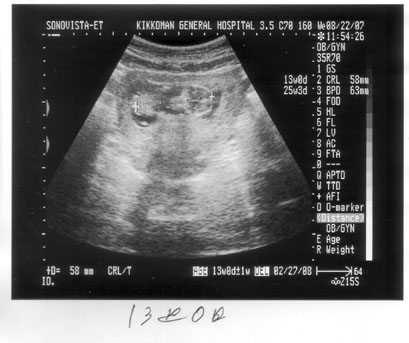

c.jpg赤ちゃんの形がはっきりしてきました。

13週目です。

手足もわかりますが、顔がカメラ側にあったので、

よく見ると目が見えます。

意識してんのか?

大きさは58㍉

頭デカッといわれました。